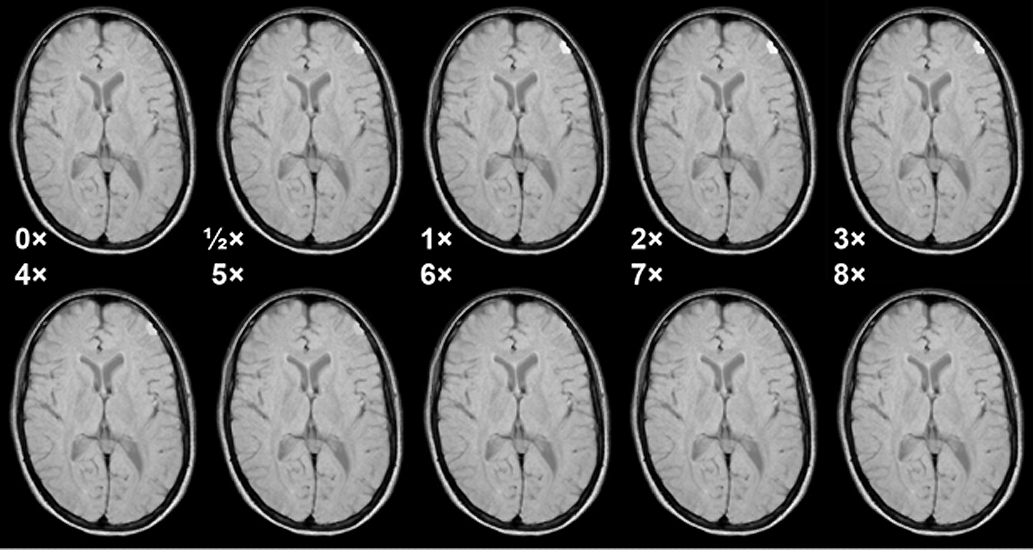

Figura 13-07:

Simulation of the influence of different tissue concentrations of Gd-based ECF space agents and mag­ne­tic field strength upon contrast in a glioblastoma. Strongly T1-weighted SE sequence, not field ad­just­ed.

Red curve = half dose; yellow = regular dose of 0.1 mmol/kg body weight; light blue = double dose; green = octuple dose.

The curves in Figure 13-07 correspond to the contrast between a glioblastoma and white matter af­ter enhancement. Before enhancement the contrast between glioblastoma and white matter is negative (the tumor is dark; its contrast behavior curve is below ½ dose but is not depicted in this figure) [⇒ Rinck 1999].

Only the regular (yellow) and double (light blue) doses give rise to sufficient con­trast at all fields. Increasing them is counterproductive (8x). Figure 13-08 shows this behavior in a meningioma.

Figura 13-08:

Simulation of the influence of different doses of a Gd-based ECF-space agent in a meningioma at 1.5 Tesla. Medium T1-weighted SE sequence. Note that at higher doses the T1 en­han­ce­ment ef­fect of the agent vanishes because T2 takes over. Best enhancement is seen at the re­com­mend­ed dose and double the recommended dose.

Simulation software: MR Image Expert®

The figures explain too that in most cases cutting the contrast dose is also counterproductive.